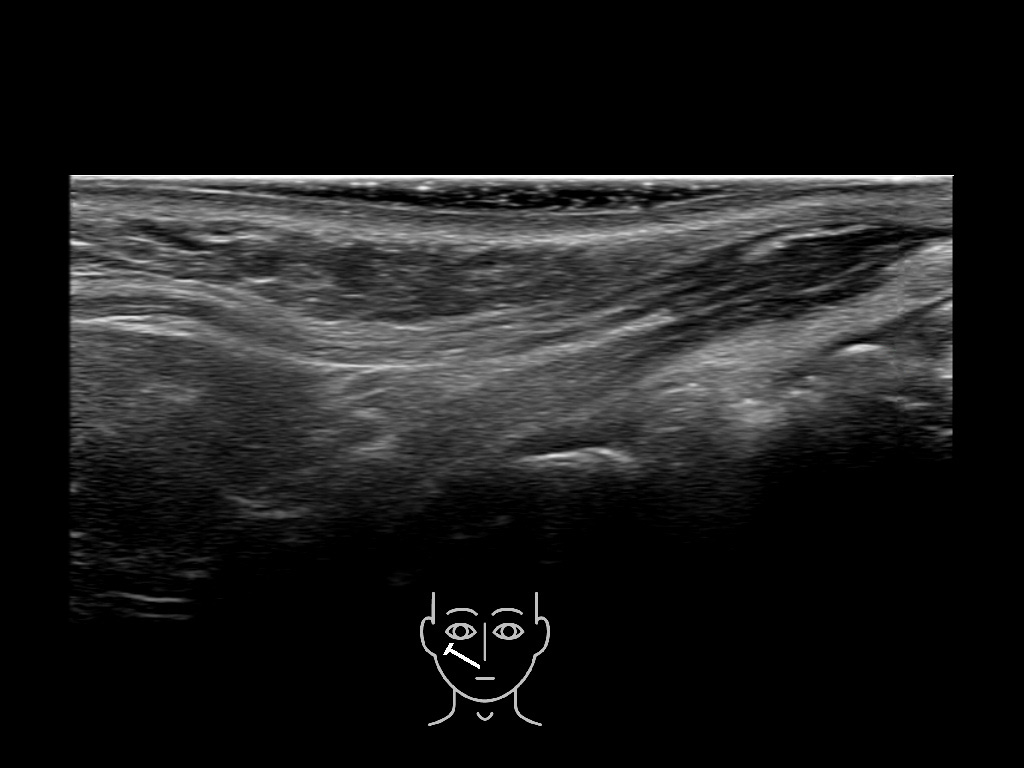

Study the first image to recognize the different layers. If you are sure about the layers, swipe to the second image to view the answer (if applicable).